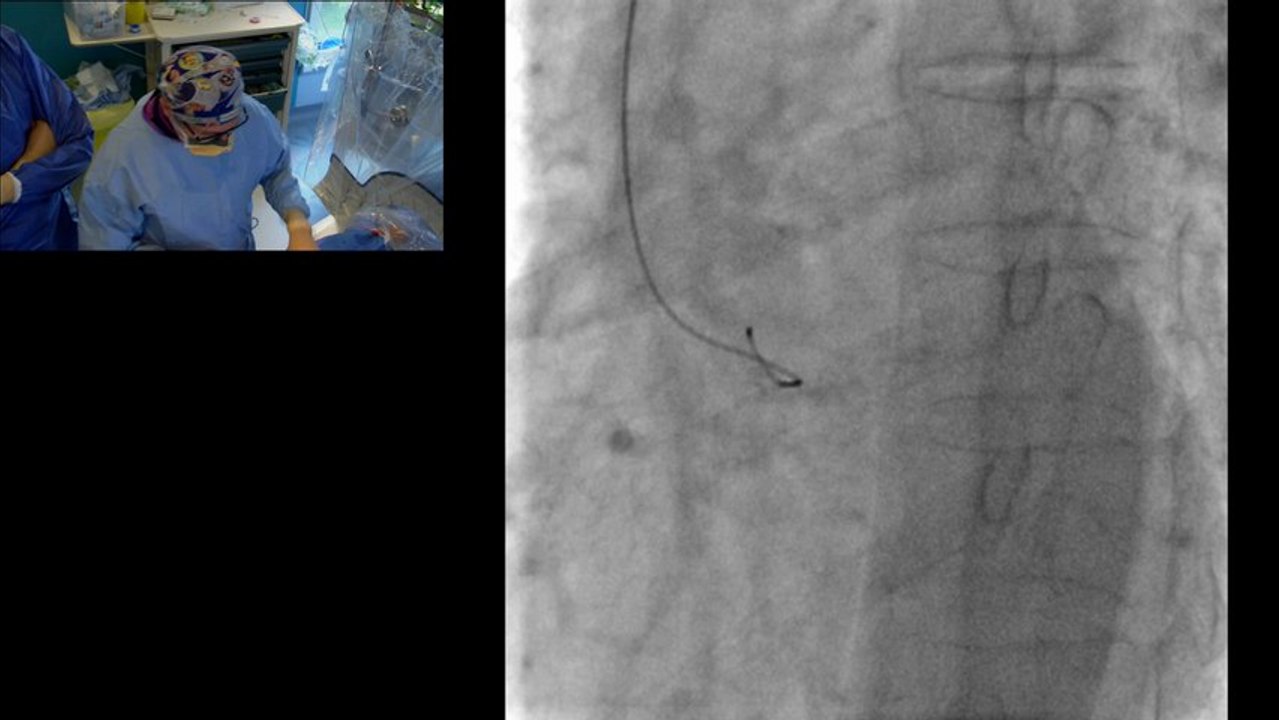

The transradial approach for coronary angioplasty became very popular at both sides of the Atlantic. By reducing local complications and simplifying patient care, this procedure became rather dominant in various European cardiovascular units. We have asked one of the best of them to share with us their current practices and the most recent innovations.

Examples of transradial stenting

Terumo Radial Intervention (TRI) solution